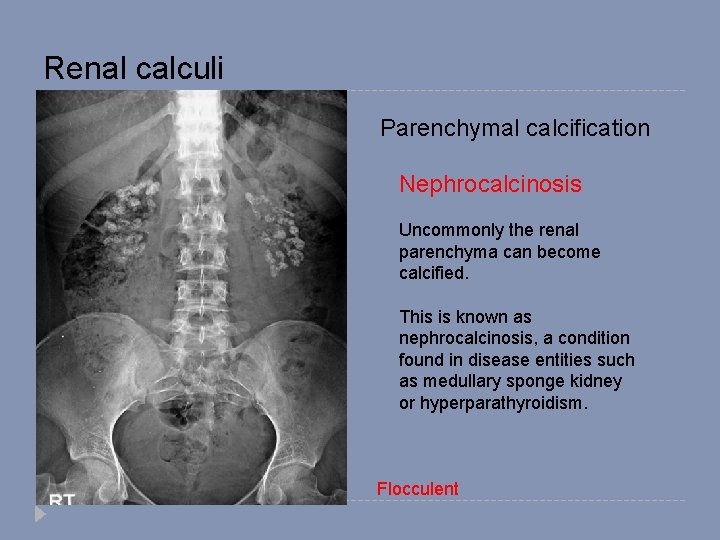

Renal calculi Parenchymal calcification Nephrocalcinosis Uncommonly the renal parenchyma can become calcified. This is known as nephrocalcinosis, a condition found in disease entities such as medullary sponge kidney or hyperparathyroidism. Flocculent